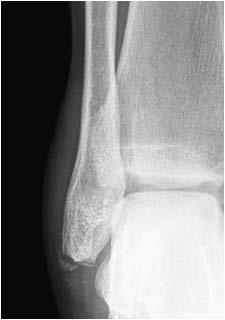

You have had a simple soft tissue injury to your ankle/foot, as part of this you may also have a chipped bone.

These injuries/fractures generally heal in a few weeks without any problems. Therefore routine Fracture Clinic follow-up is not usually necessary.